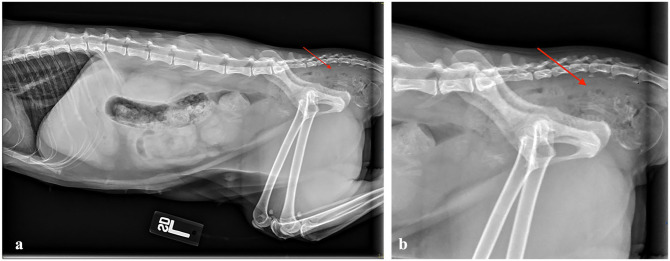

Case summary: A 2-year-old domestic shorthair queen sustained a tear in the vaginal wall through which the queen herniated a fetus during parturition. An exploratory laparotomy was performed, the patient had an ovariohysterectomy and the fetus was removed vaginally. The tear was managed medically with antibiotics, analgesics and careful monitoring. Assessment of the injury site 2 weeks later confirmed successful healing without the need for surgical intervention in the vaginal wall.

Relevance and novel information: This is the first report in veterinary medicine describing the successful medical management of a dystocia-related vaginal wall tear in a feline patient without surgical repair.